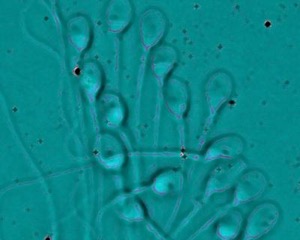

Σε αυτές τις περιπτώσεις, διαλέγουμε υγιή σπερματοζωάρια σε μικροσκόπιο μεγάλης διακριτικής ικανότητας. Κατόπιν, με μια ειδική βελόνα τρυπάμε το τοίχωμα του ωάριου εισάγοντας το σπερματοζωάριο. Την επόμενη μέρα περιμένουμε να δούμε την εξέλιξη και ποιότητα των εμβρύων.

IMSI (ενδοκυτταροπλασματική έγχυση μορφολογικά επιλεγμένων σπερματοζωαρίων)

Η μέθοδος επιλογής σπέρματος περιλαμβάνει την μορφολογική επιλογή του σπέρματος με υψηλής ανάλυσης μικροσκόπιο περίπου 5 φορές μεγαλύτερης ευκρίνειας.

Με τον τρόπο αυτό, επιλέγονται τα σπερματοζωάρια των οποίων το σχήμα και το μέγεθος υποδηλώνει καλή γενετική ποιότητα κάτι που απαιτεί εξειδικευμένη εκπαίδευση για τους εμβρυολόγους. Στη συνέχεια, τα σπερματοζωάρια εμφυτεύονται μέσα στα ωάρια με τη μέθοδο ICSI.